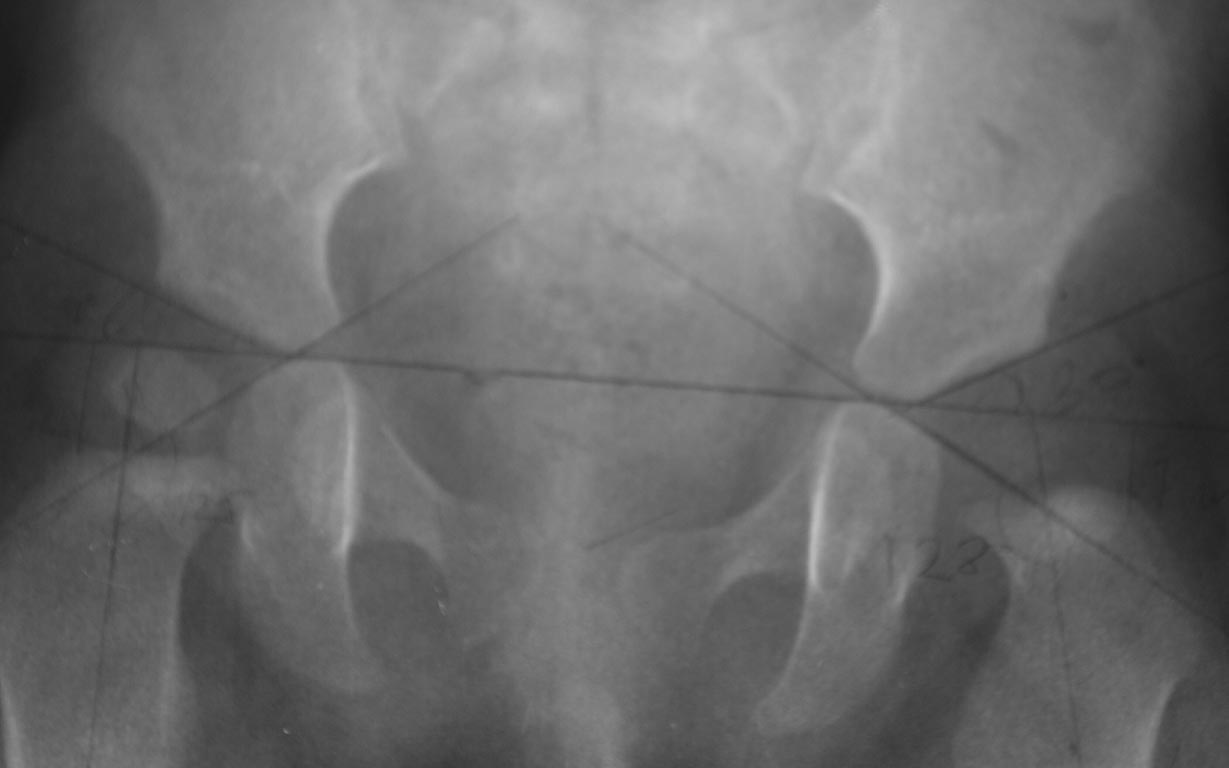

Добрый вечер уважаемые коллеги. Помогите советом, в какую клинику и к кому обратится с данной проблемой (у ребенка в возрасте 1мес. диагностирован гематогенный остеомиелит головки бедра).

Лечили консервативно (выписку и фото в динамике прилагаю). На сегодняшний день ребенку 11 мес. Детские ортопеды по месту сомневаются в тактике( в плане операции или выжидательная тактика). Хотелось проконсультироваться с теми кто занимается этой проблемой.Заранее спасибо. С ув. Андрей

По факту снимков-справа т/б сустав(снимок №6) также не в порядке - в состоянии подвывиха-головка почти на треть вне впадины, снимок №7 - непонятная укладка